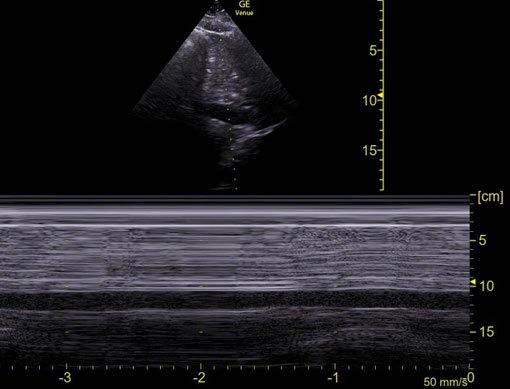

The position to measure the IVC diameter for calculating the caval index is 2-3 cm from where the IVC enters the right atrium or 2-3 cm from the diaphragm. Another available method for visualizing respiratory variation is by using M-mode, placing the cursor over the IVC, 2cm from the right atrium or 2-3 cm from the diaphragm. On the M-mode image, the inspiratory and expiratory diameters are measured at the minimum and maximum positions, respectively (Fig.1). 2

Figure 1: M-mode with cursor over the IVC